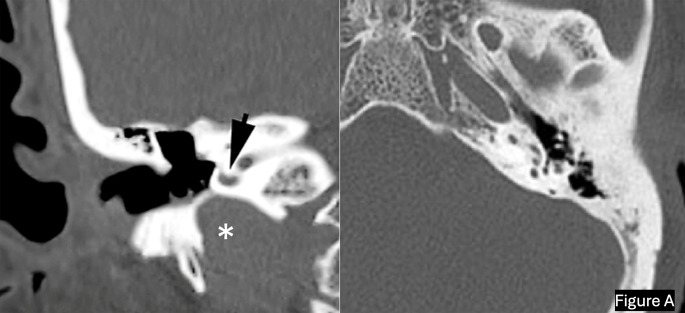

Abstract Image